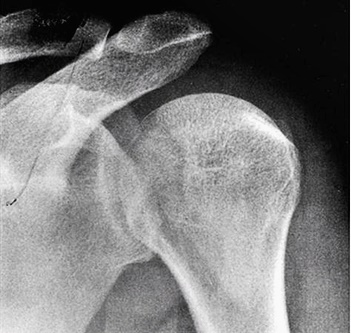

2. 모양 변형

어깨 탈구가 발생하면 정상적으로 보이지 않고 어깨의 삼각근 부위가 변형되는 모습이 관찰되기도 합니다. 탈구 시 신경 손상이 동반되는 경우 감각이상이나 마비 장애, 색깔 변화, 멍 등의 다른 변화가 나타날 수 있습니다.

어깨 탈구 치료

외상성 탈구의 경우 보존적 치료보다는 수술이 필요한 경우가 많습니다. 반면 비외상성의 경우는 보존적 치료로 증상을 개선하기도 하는데요. 먼저 정확한 진단을 통해 원인이 외상성인지 비외상성인지 판단하는 것이 중요합니다.

수술이 필요한 경우 보통 파열된 구조를 봉합하여 복원하는 수술이 시행되는데요. 복원이 불가능한 경우 비생리적인 방법의 수술이 필요하기도 합니다. 수술 이후 수주 간 보조기 사용이 필요하며 팔을 정상적으로 사용할 때까지 3개월가량 소요될 수 있습니다.